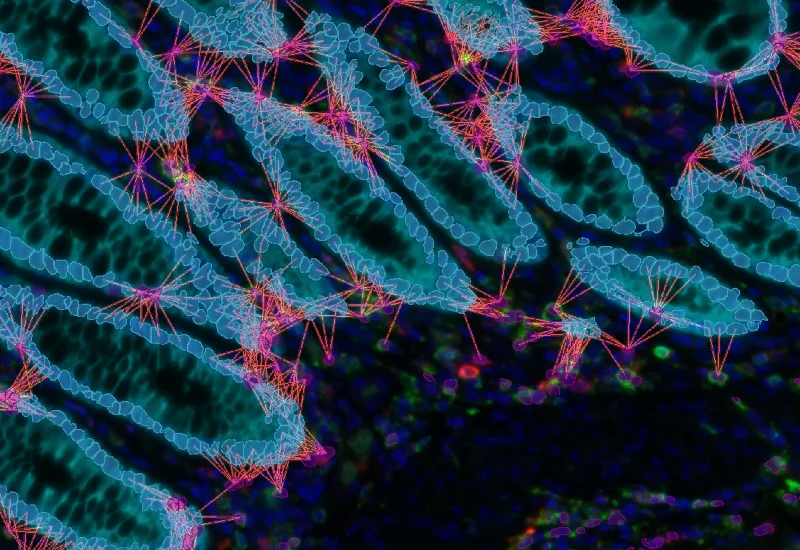

IF Cellular microenvironment

Determine phenotypes of specific IF-stained cell populations, analyze spatial relationships to neighboring cells and metastructures (e.g. vessels, tumors), and perform proximity and infiltration analyses.

phenotyping, phenotype interactions, proximity map, spatial landscape, immune cells, tumor, colon cancer, TMA, Foxp3, CD4, CK, PD-1, T regulatory cells, fluorescence